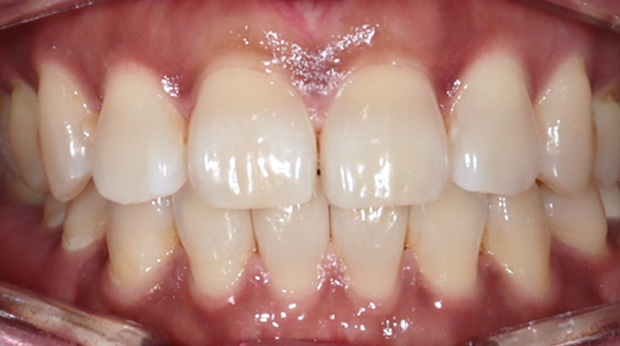

구강외과 진료

라미네이트

의식하진정법(수면마취)/임플란트